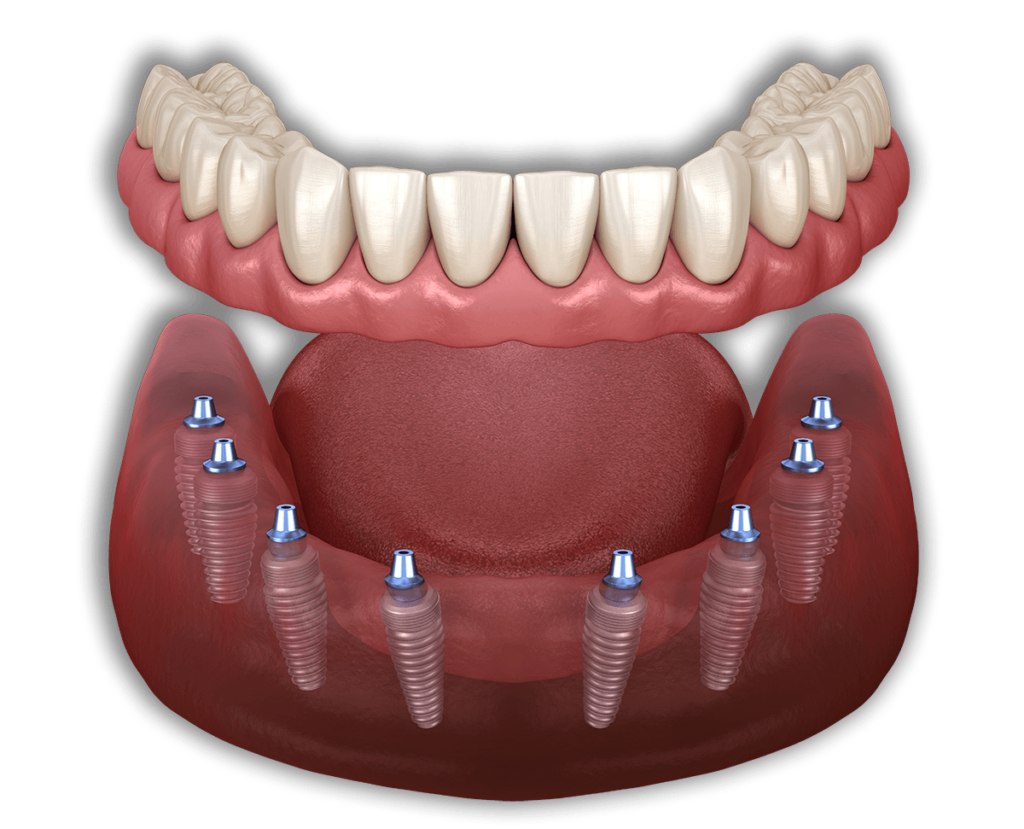

All on 4

All on 4 può creare una serie completa di denti utilizzando solo quattro impianti in ciascuna mascella. La fattibilità di ciò dipende dalla mascella e dalle circostanze specifiche. Una volta valutati i tuoi denti attuali, il livello di danno, nonché la struttura e la salute della mascella, possiamo stabilire se un impianto All on 4 è la scelta giusta. Questa procedura chirurgica utilizza otto impianti, quattro nella mascella superiore e quattro nella mascella inferiore, per supportare protesi o corone permanenti.